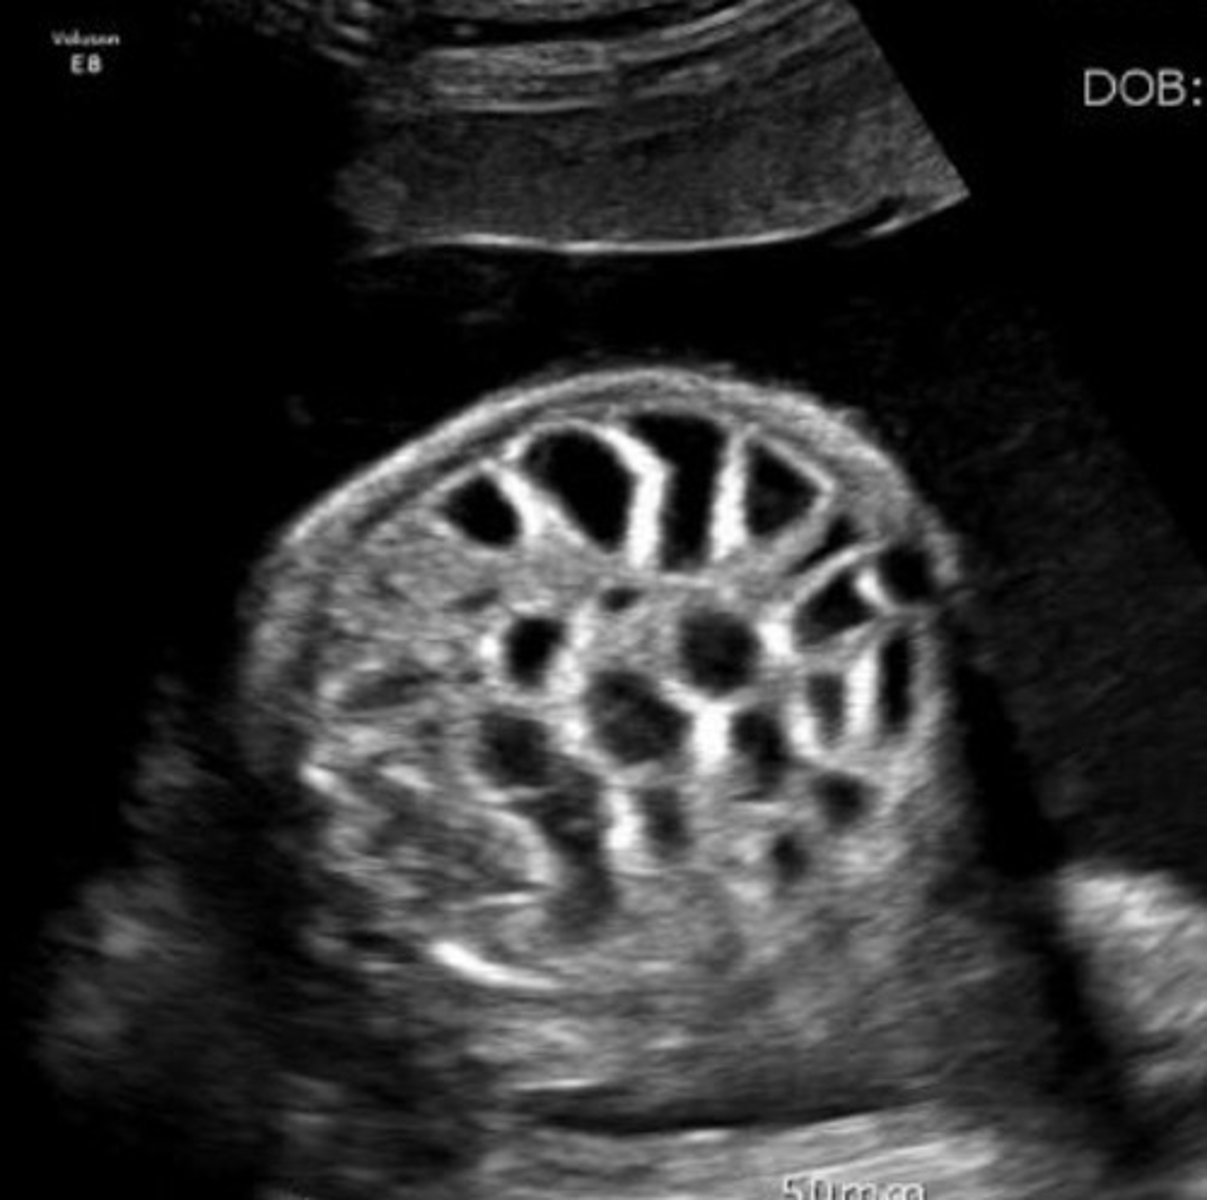

Grade 3 Hydronephrosis

Pelvis is > 10 mm

Marked dilation of calyces

Cortex is normal

Grade 4 Hydronephrosis

Mild thinning of cortex

Grade 5 Hydronephrosis

Severe thinning of cortex